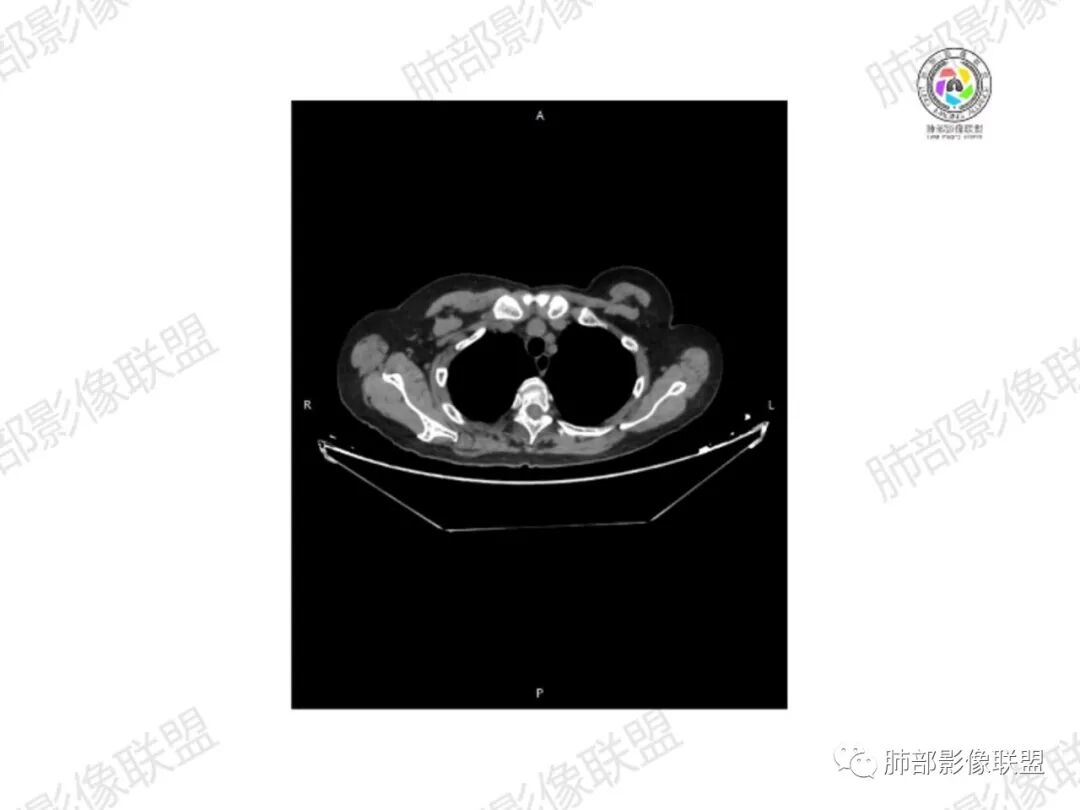

1.老年女性,直肠癌术后放疗后5年,右臀部疼痛4个月,加重半月

2.右髂骨轻度变形伴广泛骨质吸收破坏,边界不清且突破骨皮质。近中线区以溶骨性破坏为主,髂骨翼一侧则成骨性改变明显,骨表面见垂直骨针或花边样高密度瘤骨。

3.患骨多处皮质断裂,符合病理性骨折。注意折端可能会形成骨痂,但本例无论是形态还是部位都不符合骨痂。

4.患骨两旁(即盆骨内外)见边界不清的较大范围软组织快影,其间偶见骨化影。

5.双肺多发类圆形结节影,边界清楚,随机分布,其间多见钙化密度影。

6.双肺门及纵隔未见肿大淋巴结。

7.扫描范围内双侧乳腺未见明显块影。